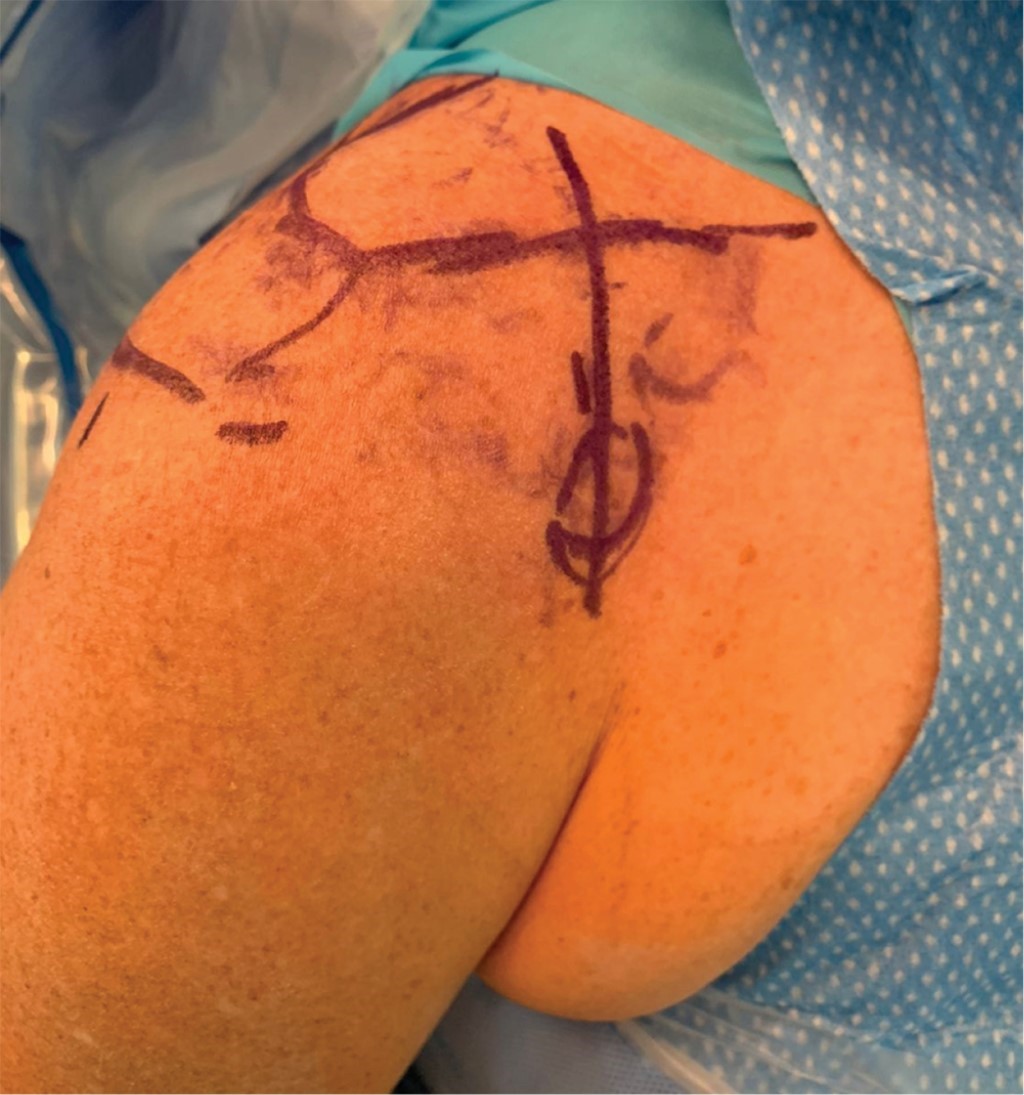

Con el paciente bajo anestesia general balanceada y previa profilaxis antibiótica, se le coloca en posición de silla de playa a 60o de flexión. Por anatomía de superficie se identifican referencias anatómicas: apófisis coracoides, acromion y la articulación AC (Figura 2). Se realiza una incisión en el borde anterior de la clavícula de 5 cm lateral a la articulación AC y se extiende hacia la apófisis coracoides siguiendo las líneas de Langer. Se diseca por planos realizando hemostasia con electrocauterio hasta identificar el músculo deltoides en la parte anterior de la clavícula y la inserción del trapecio en su cara posterior; se realiza disección roma del fascículo deltoideo en dirección a la apófisis coracoides hasta localizar la base de ésta y se pasa una gasa estéril como referencia. Se realiza exposición completa de clavícula y de articulación AC así como de sus tejidos blandos que impiden la reducción articular (Figura 3). Se resecan 3 mm del borde distal de la clavícula y se retiran tejidos blandos (remanente de ligamentos AC y disco articular) (Figura 4).

Figura 2